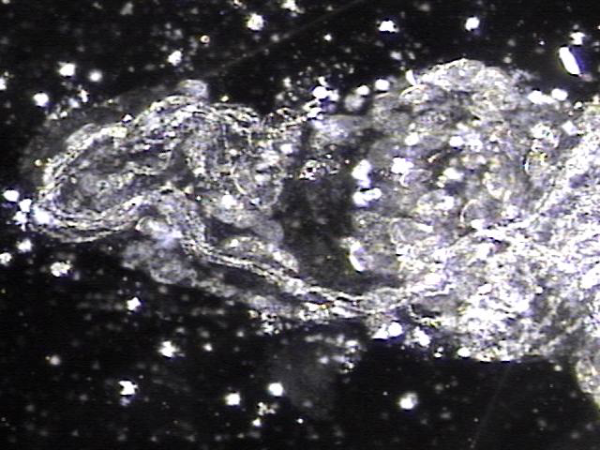

내원 첫날 전립선의 표적 치료후 치료된 정낭의 혈정액과 정자들과 염증들의 현미경학적 자료입니다.

This is a microscopic image taken after your first targeted prostate treatment, showing improvement in the seminal vesicle.

The blood-tinged fluid (hematospermia), sperm, and inflammatory cells have been successfully treated.

주 2회 전립선의 표적 치료후 사정관 입구에 막혀 있던 탈락된 상피세포와 사정관 벽에 쌓여 있던 상피 세포 덩어리가 치료 된후 관찰한 현미경학적 자료입니다.

This is a microscopic image taken after twice-weekly targeted prostate treatments. It shows the successful removal of shed epithelial cells that had been blocking the opening of the ejaculatory duct, as well as a buildup of epithelial cell clusters that had accumulated along the duct walls.